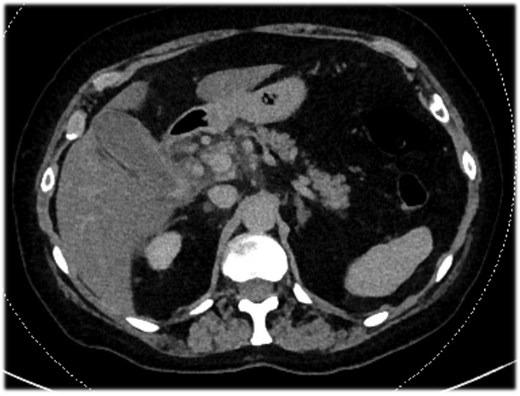

An 82-year-old female presented with a 10-day history of upper right quadrant pain, vomiting, and fever. Her medical history included an appendectomy during infancy and ongoing treatment with Euthyrox and antiplatelet therapy (aspirin 100 mg per day). Upon admission, she was presented with fever (38.1°C) and exhibited a positive Murphy sign. Laboratory tests indicated an elevated white blood cell count (WBC) of 13 G/l and an elevated C-reactive protein of 115 mg/l. CT scans revealed features of acute calculous cholecystitis (Fig. 1). Laparoscopic cholecystectomy was indicated. Intraoperatively, a perihepatic hemoperitoneum was immediately observed alongside sclero-atrophic calculous cholecystitis. Careful removal of clots on the hepatic pedicle unraveled a massive spontaneous arterial bleeding, which required immediate clamping of the artery and conversion to open surgery (Fig. 2). During the procedure, the bleeding was found to originate from a ruptured aneurysm of the left branch of the hepatic artery. Repair of the artery was neither possible nor relevant given the fragility of the arterial wall. Consequently, the left branch of the hepatic artery was excised along with the aneurysm. Cholecystectomy was performed, and cholangiography results were normal. Due to the atypical nature of the clinical situation, a comprehensive assessment was conducted postoperatively during the hospital stay. The arterial anatomopathological analysis showed no specific abnormalities. A whole-body arterial angiography-CT revealed various arterial malformations of the renal and carotid arteries, in addition to another aneurysm of the gastro-duodenal artery. The angiological workup revealed no other abnormalities, and no evidence of mycotic infection was found. The postoperative course was marked by transient cholangiopathy of the left liver, as evidenced by marked hepatic cytolysis and cholestasis (AST 3471 U/l, ALT 2450 U/l, ALP 175 U/l, GGT 365 U/l, total bilirubin 70 μmol/l, conjugated bilirubin 65 μmol/l), which showed clinical and biological improvement following a 7-day intravenous antibiotic therapy with Ceftriaxone and Metronidazole. She was discharged on postoperative day 11. At 1-month follow-up, both clinical status, laboratory parameters, and CT scan confirmed a favorable evolution, with normalization of liver function tests and arterial vascularization of the left liver through the right branch of the hepatic artery without any features of ischemic cholangiopathy.

Abdominal-CT of patient at admission, revealing signs of acute calculous cholecystitis.